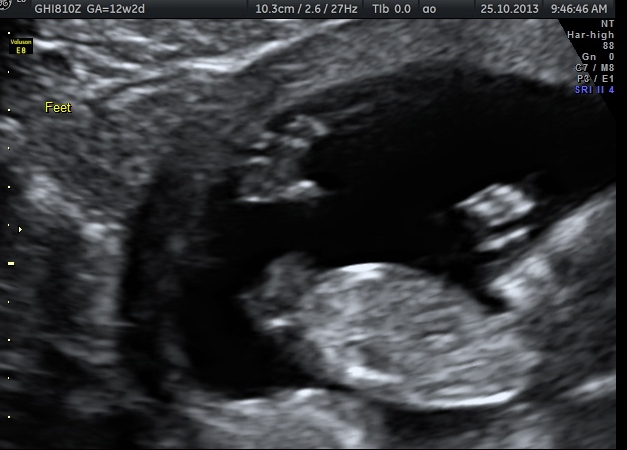

Just curious if any of you clever ladies can see any nub in either of these pics. Scan was done at 12+1 weeks.

I'm not seeing a nub.